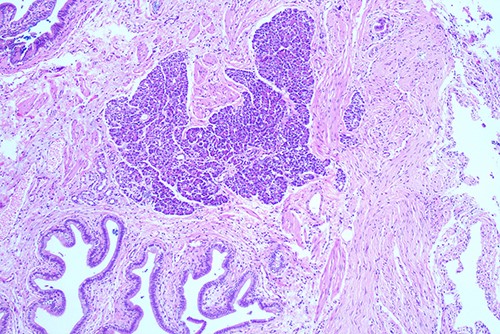

She proceeded to an elective laparoscopic cholecystectomy. At the time of her procedure, she was found to have features suggestive of chronic cholecystitis with peritoneal adhesions. Her procedure was straightforward and intraoperative cholangiogram showed a spiral cystic duct with the trifurcation of intrahepatic ducts. Her common bile duct appeared mildly dilated however tapered at the lower end and showed filling of the duodenum with no filling defects. The histology from the gallbladder showed variable fibromuscular thickening of the wall with intramural cystic Rokitansky-Aschoff sinuses, but no significant inflammation. Focal ectopic pancreatic acinar tissue (1 mm) within the gallbladder was found (Figs 1–3). There was no evidence of intestinal metaplasia, dysplasia or malignancy.

Histological examination of gallbladder ×20 showing island of ectopic pancreatic tissue adjacent to the mucosa of the gallbladder neck.